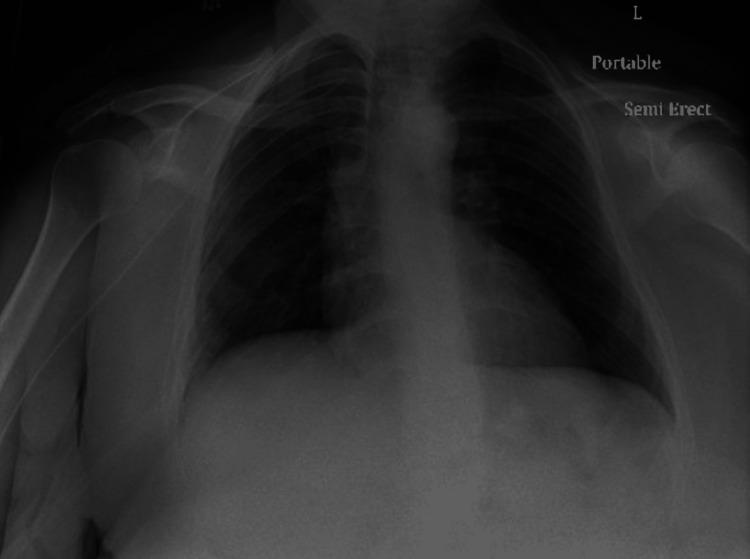

Antineutrophil cytoplasmic antibody (ANCA)-associated vasculitis is an autoimmune inflammatory disease that usually affects the small-sized vasculature, most notably of the lungs and kidneys. One of the challenges of suspecting and diagnosing the condition lies in the insidious and unclear symptoms of presentation. In this case report, we discuss the case of a patient who initially presented with solely unclear pulmonary symptoms, without other organ system dysfunction.

抗中性粒细胞胞浆抗体(ANCA)相关性血管炎是一种自身免疫性炎症性疾病,通常累及小血管,最显著的是肺部和肾脏的血管。怀疑和诊断该病的挑战之一在于其症状隐匿且不明确。在本病例报告中,我们讨论了一名患者的病例,该患者最初仅表现为不明确的肺部症状,而无其他器官系统功能障碍。